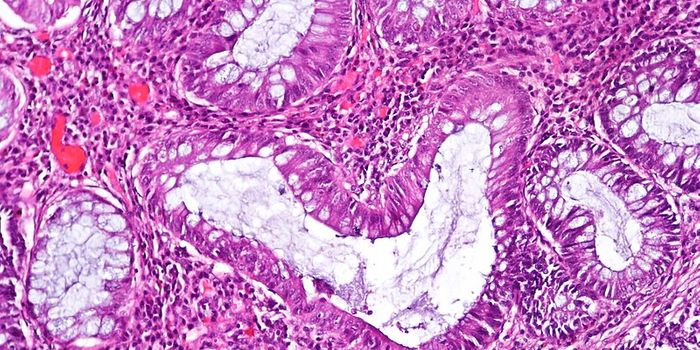

SEP 28, 2016ImmunologyA diet high in fat from specific sources is uniquely responsible for contributing to intestinal cancer through promoting ...